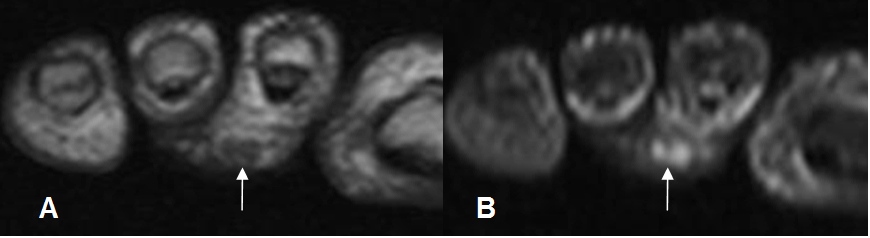

Fig 125 B. Edema en pie diabético.

A: RM axial simple en T1 y B: RM axial en T1 con contraste. Cambios inflamatorios en el tejido celular subcutáneo del pie, hipointenso en T1. No hay realce con el contraste, por inflamación sin infección.